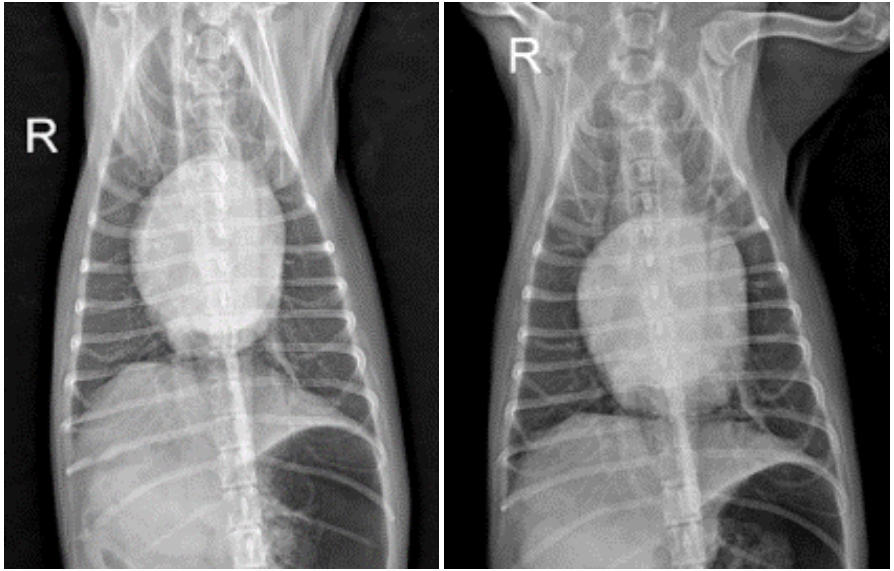

3. 입원 4일차

폐 침윤이 소실되며 폐야가 정상화되었고, 호흡 양상도 안정적인 상태를 유지하였습니다. 염증 수치 역시 호전되어 항생제를 중단하였으며, 상태가 충분히 안정된 것을 확인한 후 내복약으로 전환하여 통원 치료로 전환하였습니다.

입원 3일차(좌), 입원 4일차 (우)